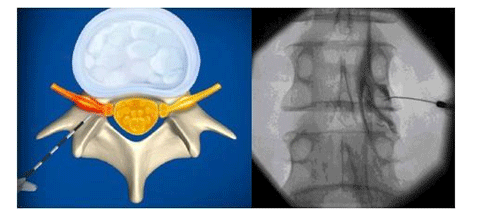

º´º¯ÀÇ ÇØ´ç ½Å°æ¸· ÁÖÀ§³ª »Ñ¸®½Å°æ ÁÖÀ§¿¡ ÁÖ»ç¾àÀ» ÁÖÀÔÇÏ¿© ½Å°æÁÖÀ§ÀÇ ¿°Áõ ¹ÝÀÀÀ» ÁÙÀÌ°í ½Å°æ¸·À¸·ÎÀÇ ¹Ì¼¼Ç÷·ù¸¦ Áõ°¡½Ã۰í, ½Å°æÁÖÀ§ÀÇ ±¹¼Ò ¸¶ÃëÈ¿°ú·Î Áõ»óÀ» È£Àü½ÃŰ´Â ¹æ¹ýÀ¸·Î ¸ñ/Ç㸮 µð½ºÅ©º´, ôÃßÇùÂøÁõ, ôÃßÀü¹æÀüÀ§Áõ, ¸¸¼º ¿äÅë, ôÃß ºÐ¸®Áõ µî¿¡ ¿ì¼±ÀûÀ¸·Î Ä¡·á ÇÒ¼ö ÀÖ½À´Ï´Ù.